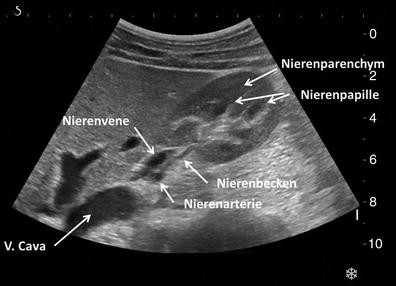

Ultraschall Der Nieren Und Harnwege Deximed

Sonographie Der Niere Des Retroperitoneums Und Der Harnblase Springerlink